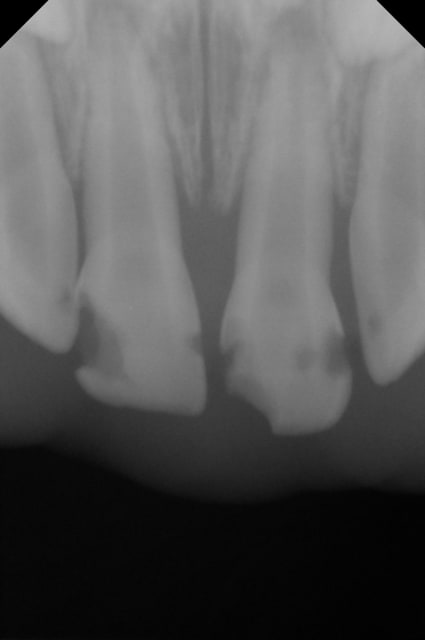

La 51 semble nécrosée aussi.

Je pense faire une pulpec sur la 51 par contre.

J'ai deja fait quelques pulpec sur des molaires temporaires sans succes, ya t-il de meilleurs taux de réussite sur les incisives ?

Les pulpectomies sur dents temporaires nécrosées se font si la dent est en stade de stabilisation (de 2à 4 ans pour les centrales) et s'il n'y a pas d'atteinte osseuse. Mais dans ton cas, j'ai l'impression qu'il y en a une, non? On ne voit pas bien l'apex de 51.